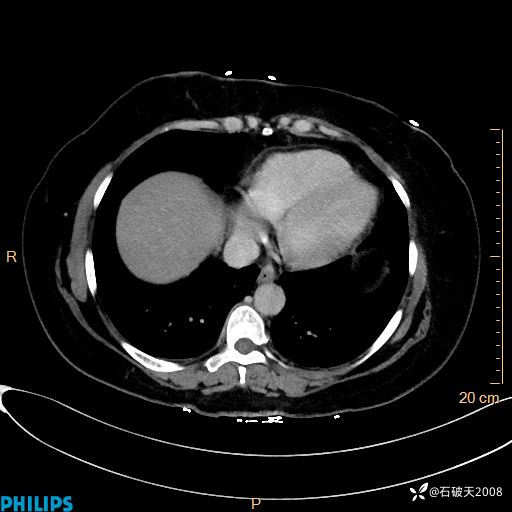

纵隔窗

静脉期